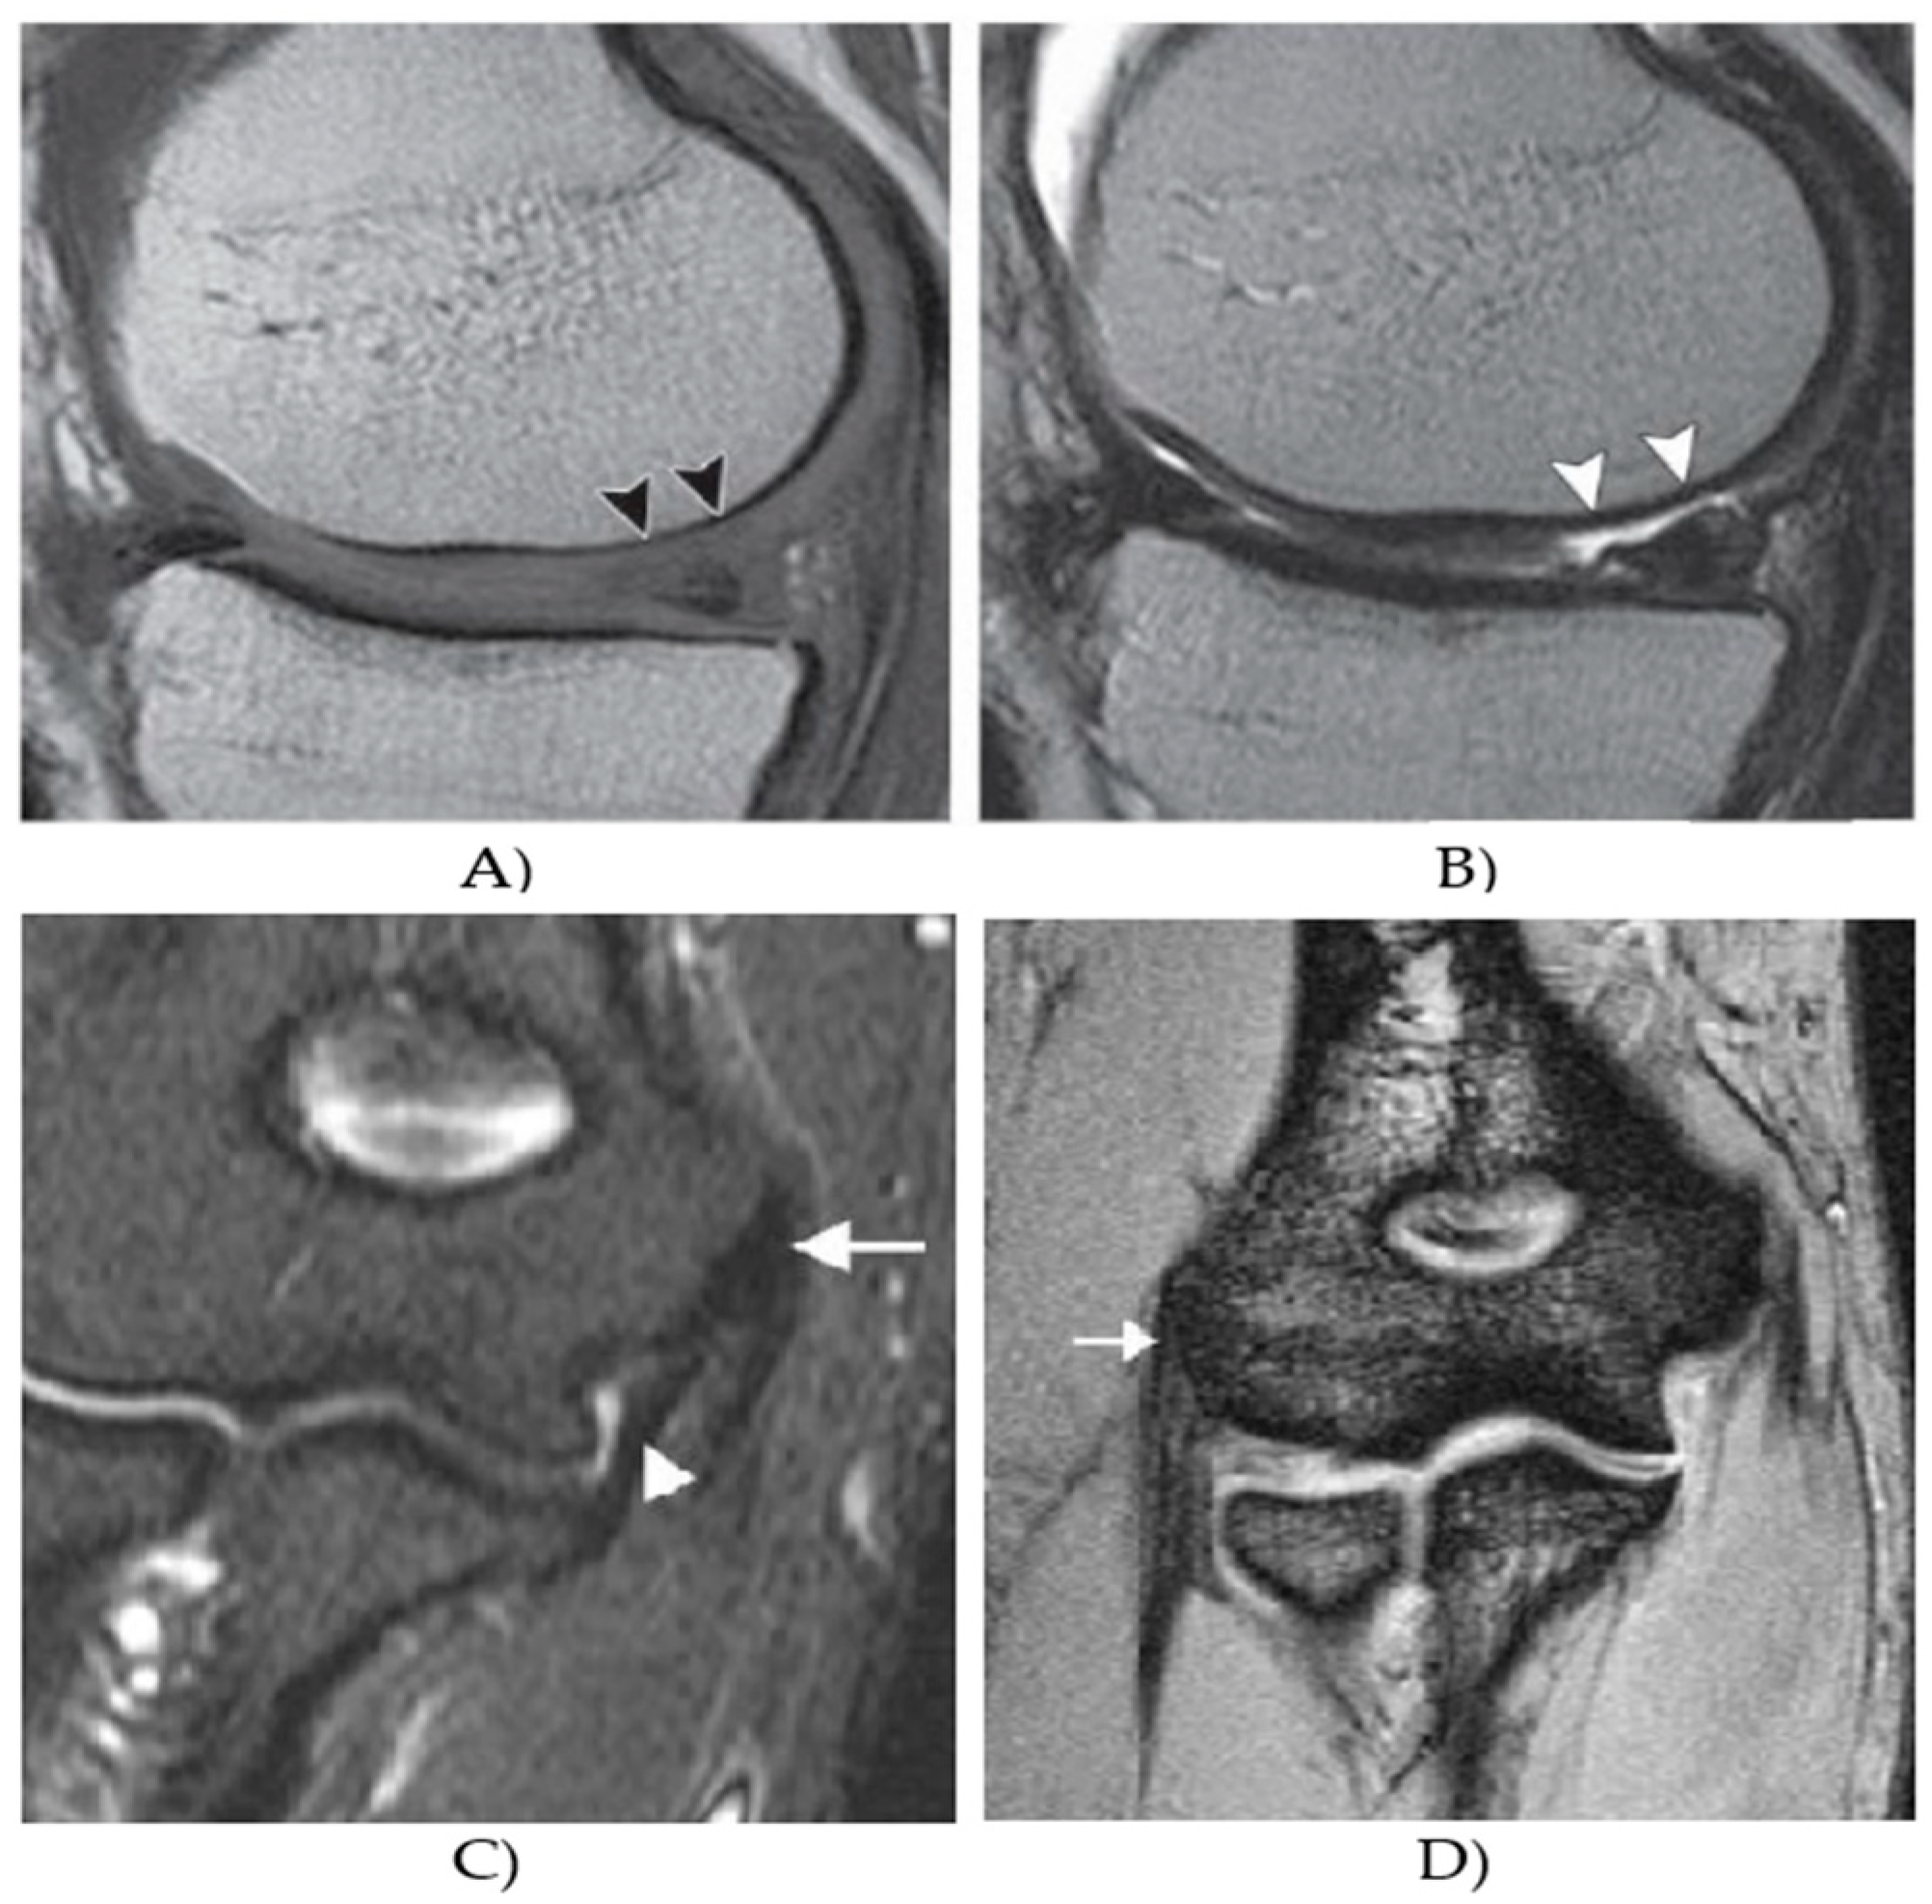

In this section, we provide a quantitative evaluation and performance analysis of the NLM filter, incorporating the patch and similarity information in the contrast of standard NLM filter and conventional local mean approaches, including average and median filter to demonstrate its robustness in various environment, caused by the effect of additive noise generators with dynamic noise intensity. Since the filtration procedure, providing smoothing of image area is a common part of the object identification from MR images, we also provide a quantitative analysis of a regional segmentation performance, when using the proposed filter. Figure 1 represents an example of the MR database, which we use for the testing.

Figure 1.

Example from MR datasets: (A) T1 weighted image, showing a weak contrast between the cartilage surface and synovial fluid, (B) proton density-weighted image, (C) coronal fat-saturated proton density-weighted image of elbow muscle, showing a low signal intensity of the common flexor tendon, which is located at the medial epicondyle (arrow), and (D) coronal gradient echo image of elbow muscle, showing a normal manifestation of a normal extensor tendon at the lateral epicondyle (arrow).